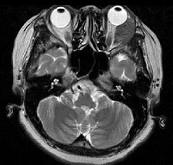

女,52岁,左眼球突出二十余年,T、T均正常,影像检查如图所示,应诊断为()A.错构瘤B.脂肪瘤C.畸胎瘤D.血管瘤E.炎性假瘤

问题 女,52岁,左眼球突出二十余年,T、T均正常,影像检查如图所示,应诊断为()

选项 A.错构瘤 B.脂肪瘤 C.畸胎瘤 D.血管瘤 E.炎性假瘤

答案 A